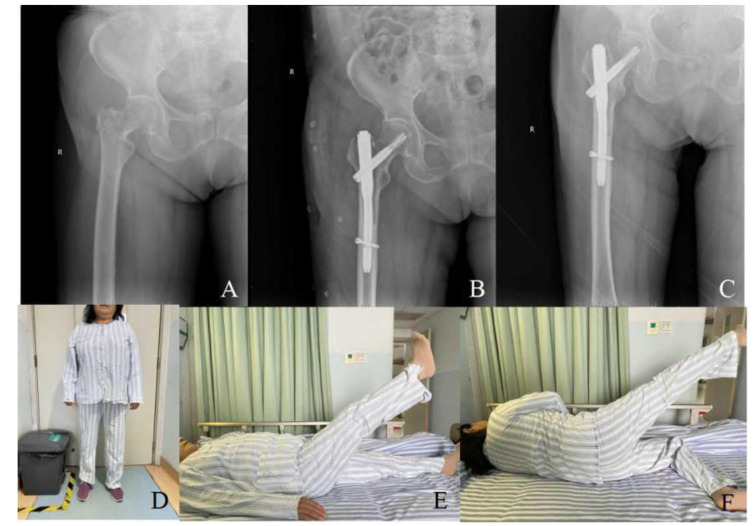

Methods: Eighty-two elderly patients with intertrochanteric femoral fractures treated at Xiangyang No. 1 People's Hospital affiliated with Hubei University of Medicine from December 2021 to 2022 were retrospectively analyzed. They were categorized into three surgical groups: PFBN (22 cases), Inter-TAN (20 cases), and PFNA (40 cases). Preoperative demographics and fracture characteristics were compared, alongside intraoperative and postoperative metrics like operative time and complication rates.

Results: In the PFBN group, operative time, fluoroscopy use, blood loss, and transfusion were higher, but postoperative weight-bearing, healing, and hospital stay were shorter compared to the Inter-TAN and PFNA groups (P<0.05). Inter-TAN had a significantly shorter postoperative weight-bearing time than PFNA (P<0.001). Other compared factors showed no significant differences between groups (P>0.05), including complication rates and scores at 6-month follow-up.

Conclusions: PFBN, a novel surgical approach for intertrochanteric fractures in elderly patients, outperforms Inter-TAN and PFNA by accelerating early weight-bearing and hastening fracture recovery.